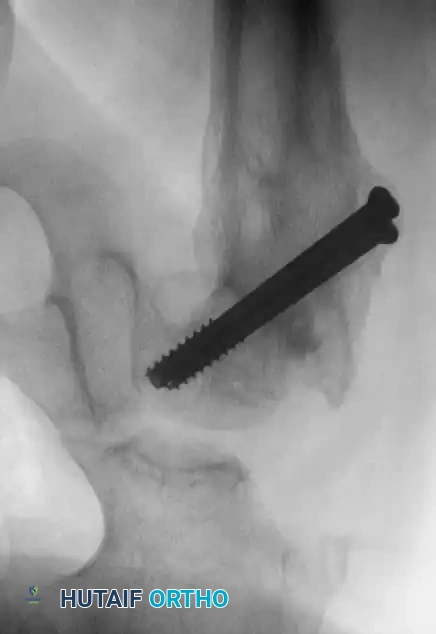

Management of Type III: Cervicotrochanteric Fractures

Type III fractures experience massive shear forces. While historically treated with pins, the high rate of varus collapse and nonunion has shifted the paradigm toward more rigid constructs.

- Reduction: Closed reduction on a fracture table.

- Fixation: For "low" cervicotrochanteric fractures, simple screw fixation is often inadequate due to the lack of cortical support inferiorly.

- Technique: Utilize a pediatric dynamic hip screw (DHS) or a cannulated screw with an attached side plate. This converts shear forces into compressive forces and rigidly maintains the neck-shaft angle.

Fig. 14: Displaced Type III cervicotrochanteric fracture prior to intervention.

Fig. 15: Intraoperative reduction of the Type III fracture.

Fig. 16: Final fixation utilizing a cannulated screw and attached side plate to neutralize shear forces.